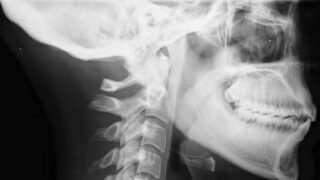

Una compagina medica Israeliana (Zebra Medical Imaging) ha siglato un accordo con un fornitore di servizi medicali statunitense che potrebbe cambiare la modalità  in cui vengono diagnosticate alcune patologie riscontrate a seguito di un’indagine radiografica.

Le due aziende stanno sviluppando grazie a una rete neurale artificiale un sistema che sia in grado di confrontare le radiografie dei pazienti con un database proprietario che include un catalogo di milioni di immagini con rispettive diagnosi. Il progetto ha l’obbiettivo di offrire al radiologo le immagini già  accompagnate da un’ipotesi di diagnosi generata dall’intelligenza artificiale così da eliminare i costi altissimi imputabili a diagnosi errate e pesare meno sul sistema di servizio sanitario.

Se l’esperimento dovesse dare buoni esiti potremmo immaginare in un prossimo futuro diagnosi sempre più precoci di patologie ossee, cardiovascolari e polmonari, ovvero di tutte quelle che sfrutterebbero i vantaggi di un’analisi preliminare comparativa con migliaia di dati che andrebbe a sommarsi a quella del medico. Ci sono diversi progetti che hanno come protagonista l’utilizzo di un’intelligenza artificiale: per fare un esempio Ibm ha speso gli ultimi anni risorse per Watson, un supercomputer in grado di analizzare e acquisire grandi quantità  di informazioni dal testo, aumentando così la base di conoscenza sulla quale verrà  formato il processo di comprensione successivo. In concreto un computer in grado di imparare.che ha già  trovato spazio per la ricerca clinica oncologica.